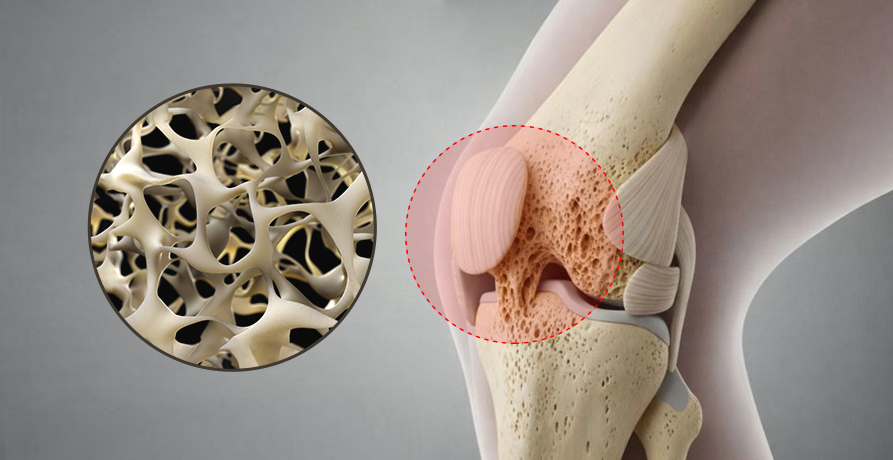

OSTEOPOROSIS

골다공증은 뼈 건강을 위해

꾸준한 관리가 필요합니다.

골다공증은 뼈의 밀도와 강도가 감소하여

작은 충격에도 쉽게 골절이 발생할 수 있는 질환입니다.